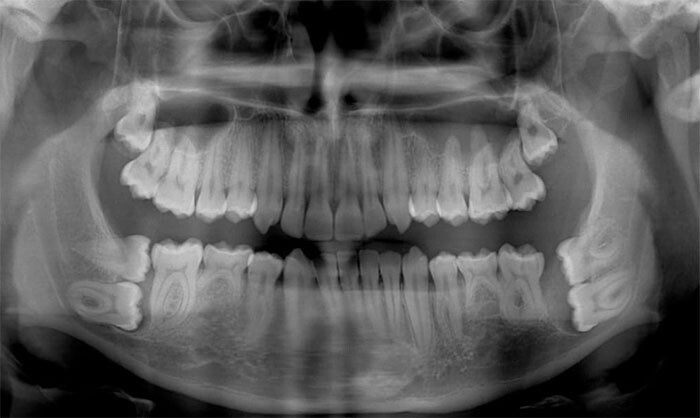

«У меня клейдокраниальный дизостоз, или, если проще, у меня в челюсти много лишних „запасных“ зубов»

«Я дантист, но рентгеновские снимки детей 6-12 лет меня немного пугают до сих пор»